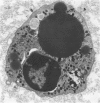

The morphology and function of cytoplasmic lipid bodies in human neutrophils were evaluated. By transmission electron microscopy, neutrophil lipid bodies were cytoplasmic inclusions, usually several microns in diameter, that occasionally coalesced to attain a diameter up to 7 microM. Neutrophil lipid bodies were not enveloped by membrane but were often surrounded by a more electron-dense shell at their periphery. Normal peripheral blood neutrophils contained an average of approximately one lipid body per cell. Lipid bodies appeared in greater numbers in neutrophils from inflammatory lesions. Perturbation of neutrophils during conventional methods of cell isolation and purification modestly increased lipid body numbers in neutrophils, whereas incubation of neutrophils with 1 microM oleic acid rapidly induced lipid body formation over 30 to 60 minutes. After granulocytes were incubated for 2 hours with 3H-fatty acids, including arachidonic, oleic, and palmitic acids, electron microscopic autoradiography demonstrated that lipid bodies represented the predominant intracellular sites of localization of each of the three 3H-fatty acids. There was lesser labeling noted in the perinuclear cisterna, but not in cell membranes. Virtually all of each of the three 3H-fatty acids incorporated by the neutrophils were esterified into chromatographically resolved classes of neutral lipids or phospholipids. These findings indicate that cytoplasmic lipid bodies are more prominent in neutrophils in vivo engaged in inflammatory responses and that these organelles in human neutrophils function as sites of deposition of esterified, incorporated fatty acids.